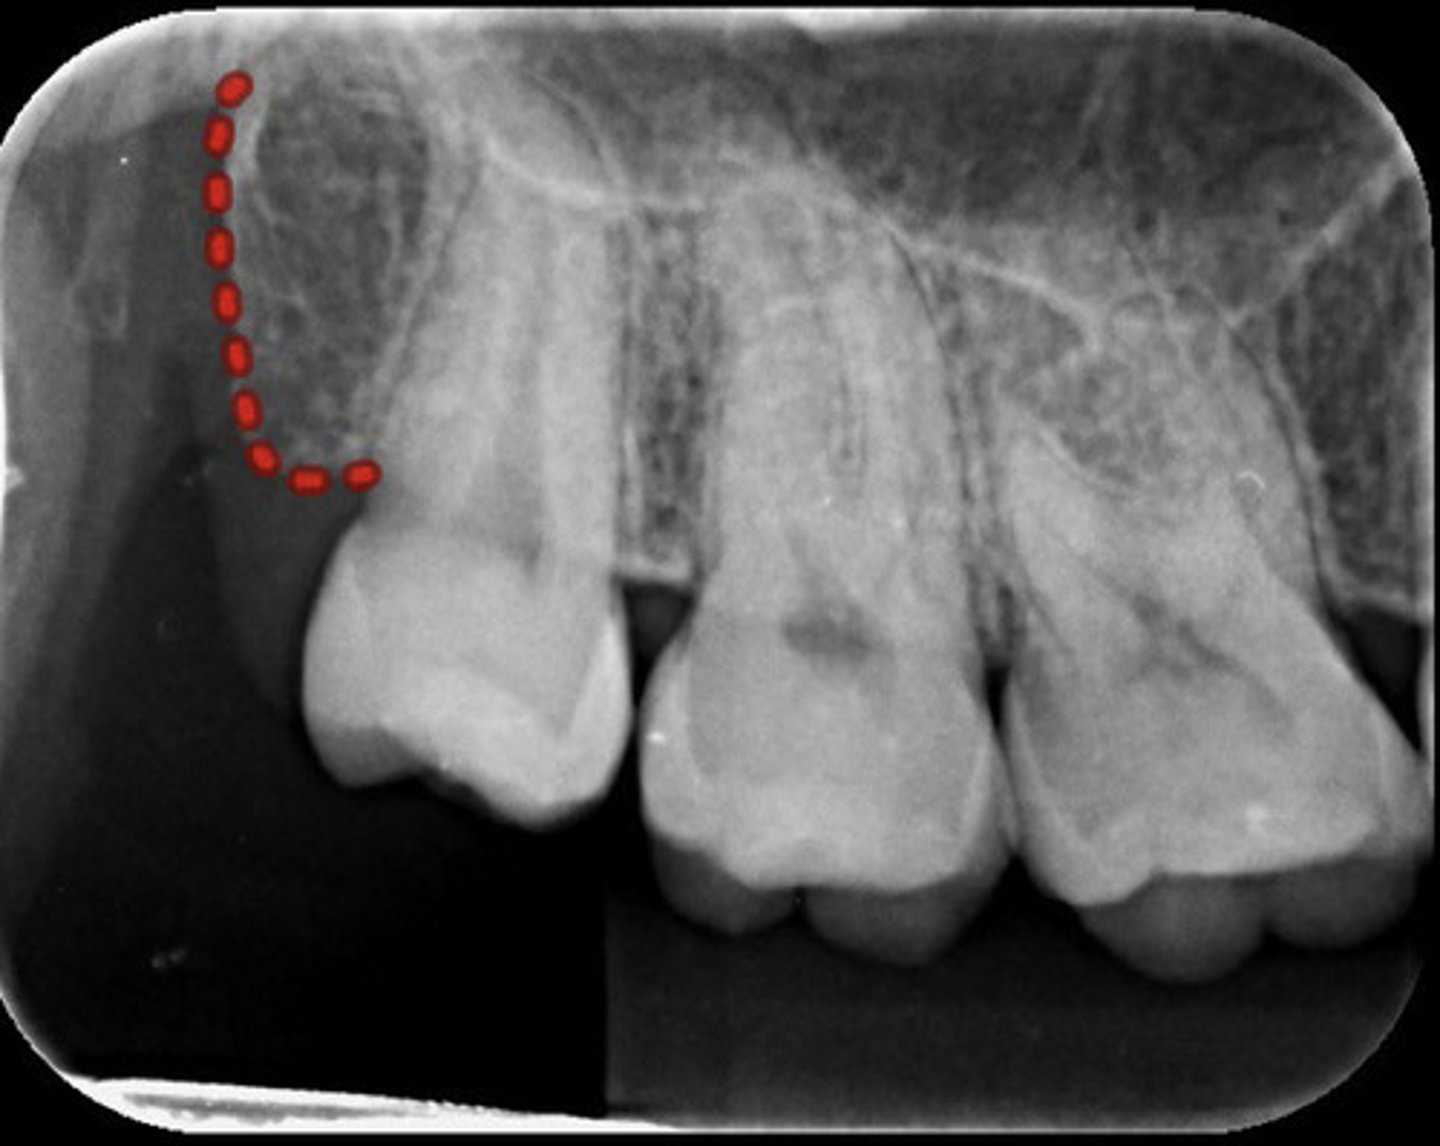

What is the red dotted line circling?

Maxillary sinus